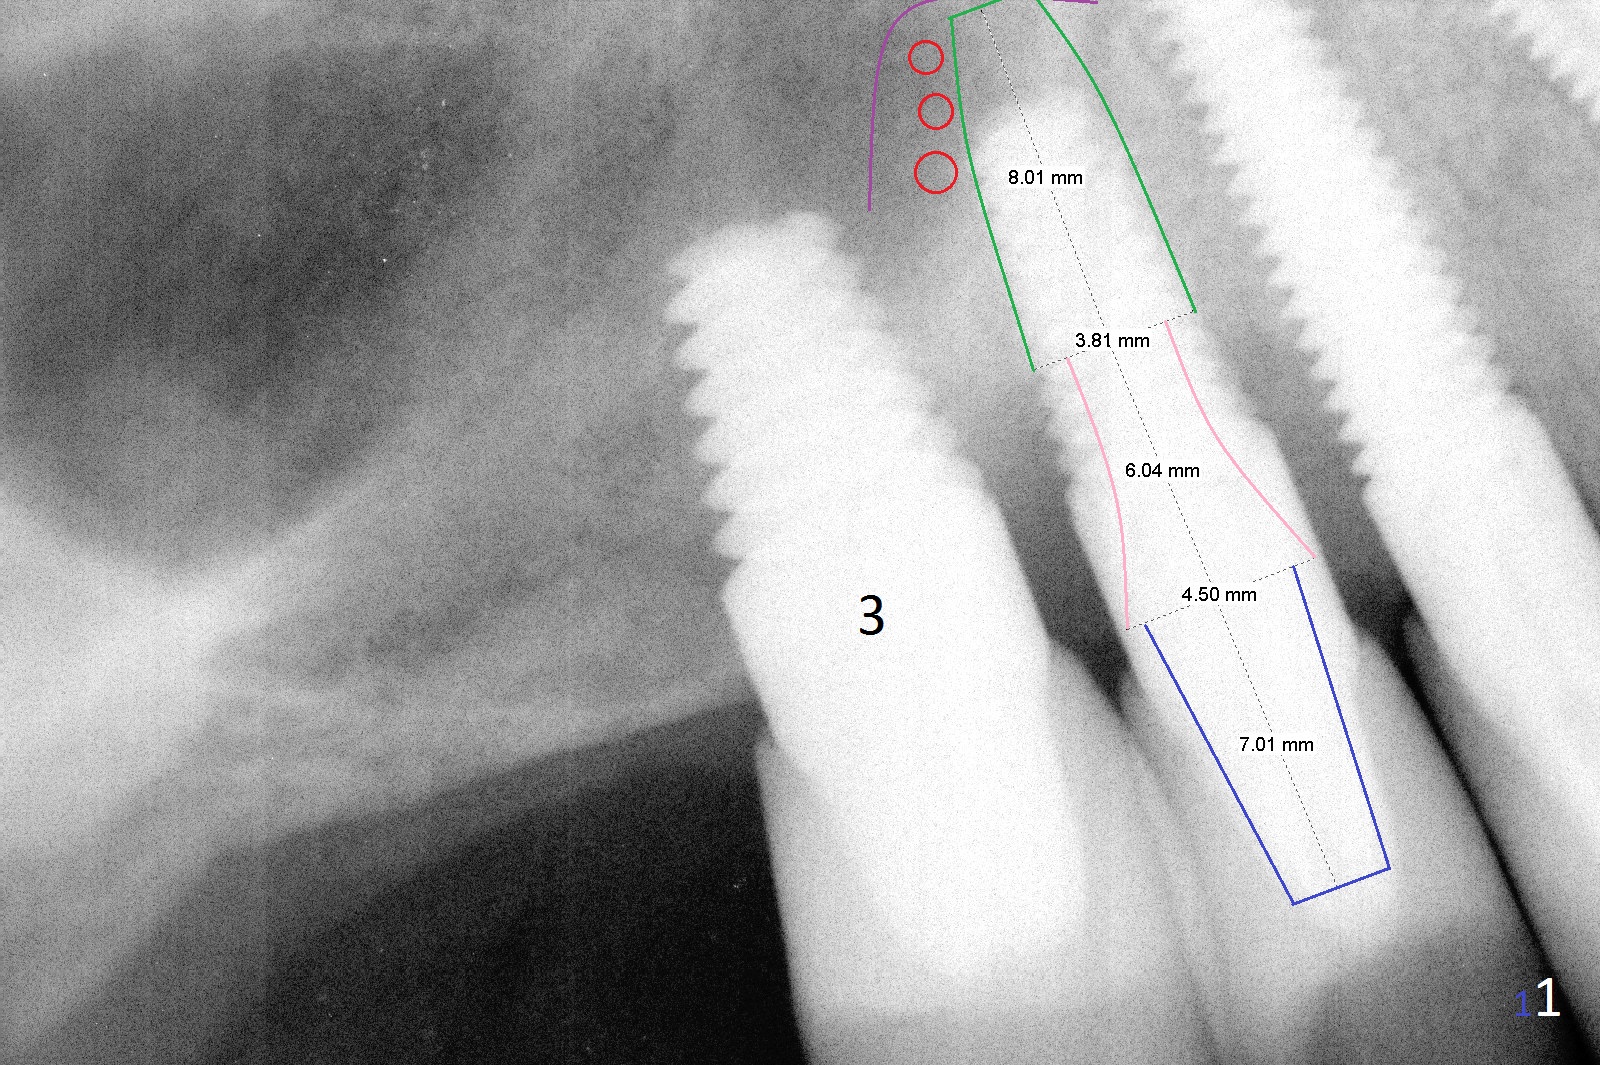

A 58-year-old man has two types of implant complications: periimplantitis at #4 (in spite of 2 bone graft surgeries, Fig.1) and abutment loosening at #14 and repeatedly 19 (probably due to bruxism, Fig.2,3).

For the implant #4 (4.5x14 mm), there are 2 options: exposed thread or implant removal. Either way, make an ample incision. Prepare long diamond burs. Soak several pieces of gauze in 1:1000 Epinephrine. The implant will be removed using 5/6 mm trephine bur or surgical handpiece, followed by immediate placement of a bone-level implant with the longest abutment cuff (Fig.1: 6 mm (pink)). Insert PRF (purple line, 4-5 tubes of blood) and allograft (red circles) prior to implantation. The implant/crown ratio is poor, place a long healing abutment or cemented abutment with the shortest abutment height (4 mm vs. 7 mm of the final one (Fig.1 blue, 6-8 months of healing)). If the site is unfavorable for implantation, a 3-unit bridge will be fabricated.